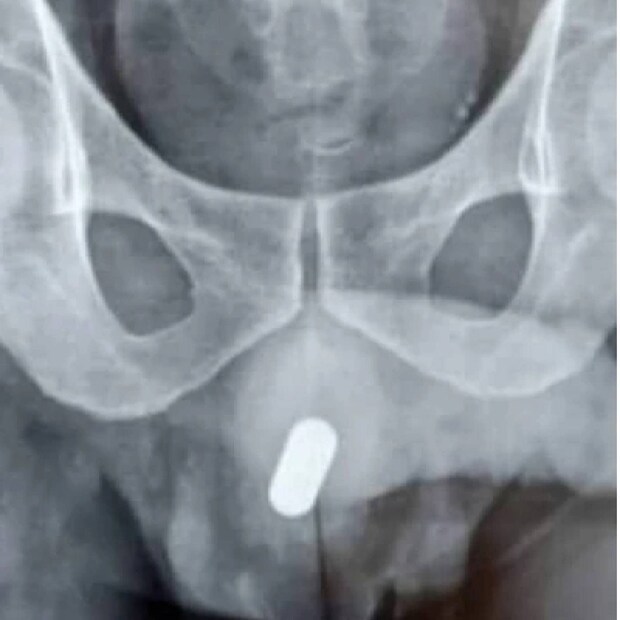

സ്വന്തം ജനനേന്ദ്രിയത്തിൽ ഡബിൾ A സൈസ് ബാറ്ററി (AA battery) കയറ്റി യുവാവ്. സങ്കീർണ്ണമായ അവസ്ഥയിൽ നിന്നും ഇയാൾക്ക് 24 മണിക്കൂറിനു ശേഷം ഡോക്ടർമാർ മോചനമേകി. പുതിയ ഡിസ്കവറി+ സീരീസായ “ദിസ് കെയിം ഔട്ട് ഓഫ് മി” എന്ന ചിത്രത്തിന് ഒരുപക്ഷെ ഈ വിചിത്രാനുഭവം അനുയോജ്യമായേക്കും. സ്വന്തമായി നടത്തിയ പരീക്ഷണം കൈവിട്ടു പോയതോടെയാണ് ഇയാൾ ആശുപത്രിയെ സമീപിച്ചത് (പ്രതീകാത്മക ചിത്രം)

പേര് വെളിപ്പെടുത്താത്ത 49 കാരൻ ആശുപത്രിയിൽ റിപ്പോർട്ട് ചെയ്ത് തന്റെ ജനനേന്ദ്രിയത്തിൽ 24 മണിക്കൂർ ആയി ചാർജിംഗ് ഉപകരണം ഉണ്ടെന്ന് ഡോക്ടർമാരെ അറിയിച്ചതിനെ തുടർന്നാണ് പരാജയം വെളിച്ചത്ത് വന്നത്. മൂത്രമൊഴിക്കാൻ ശ്രമിക്കുമ്പോഴെല്ലാം അയാൾക്ക് പൊള്ളൽ അനുഭവപ്പെട്ടതായും റിപ്പോർട്ടുണ്ട് (പ്രതീകാത്മക ചിത്രം) -തുടർന്ന് വായിക്കുക-

ഇറാനിയൻ പൗരനായ ഇയാൾ ടെഹ്റാനിലെ ഒരു ആശുപത്രിയിലാണ് ചികിത്സ തേടിയത്. മെഡിക്കൽ ജേണലിൽ പ്രസിദ്ധീകരിച്ച പുതിയ കേസ് പഠനമനുസരിച്ച്, ഒരു തുടർ സന്ദർശന വേളയിൽ, ഡിസ്യൂരിയ ഉൾപ്പെടെയുള്ള തടസ്സപ്പെടുത്തുന്നതും പ്രകോപിപ്പിക്കുന്നതുമായ ലക്ഷണങ്ങൾ ആവർത്തിച്ചുവന്നു. മൂത്രത്തിന്റെ ശക്തി കുറയുന്നു എന്നും ഇയാൾ പരാതിപ്പെട്ടു (പ്രതീകാത്മക ചിത്രം)

അതിനിടയിൽ, തുടർന്നുള്ള എക്സ്-റേകൾ മൂത്രനാളിയിൽ ഗുരുതരമായ പാടുകൾ വെളിപ്പെടുത്തി എന്ന് ന്യൂയോർക് പോസ്റ്റ് റിപ്പോർട്ടിൽ പറയുന്നു. ഇത് ട്യൂബിലൂടെ ഒഴുകാൻ കഴിയുന്ന ദ്രാവകത്തിന്റെ അളവ് കുറയ്ക്കുന്നു. ബാറ്ററിയിലെ വിഷാംശം കലർന്ന രാസവസ്തുക്കൾ മൂലമാകാം വടുക്കൾ രൂപപ്പെടാൻ കാരണമെന്ന് ഡോക്ടർമാർ അനുമാനിച്ചു (പ്രതീകാത്മക ചിത്രം)

എന്നിരുന്നാലും, മാനസിക രോഗത്തിന്റെ ചരിത്രമില്ലാത്തതിനാൽ, ഇയാളുടെ കേസ് പ്രത്യേകിച്ച് വിചിത്രമാണെന്ന് ഡോക്ടർമാർ കണ്ടെത്തി. ശാശ്വതമായ കേടുപാടുകൾ തടയാൻ, ശസ്ത്രക്രിയാ വിദഗ്ധർ രോഗിയുടെ പെരിനിയം (ലിംഗത്തെയും മലദ്വാരത്തെയും ബന്ധിപ്പിക്കുന്ന ടിഷ്യു) തുറന്നു. അങ്ങനെ വൃഷണങ്ങൾക്ക് ദോഷം വരുത്താതെ മൂത്രനാളിയിലേക്ക് പ്രവേശിക്കാൻ സാധിച്ചു (പ്രതീകാത്മക ചിത്രം)